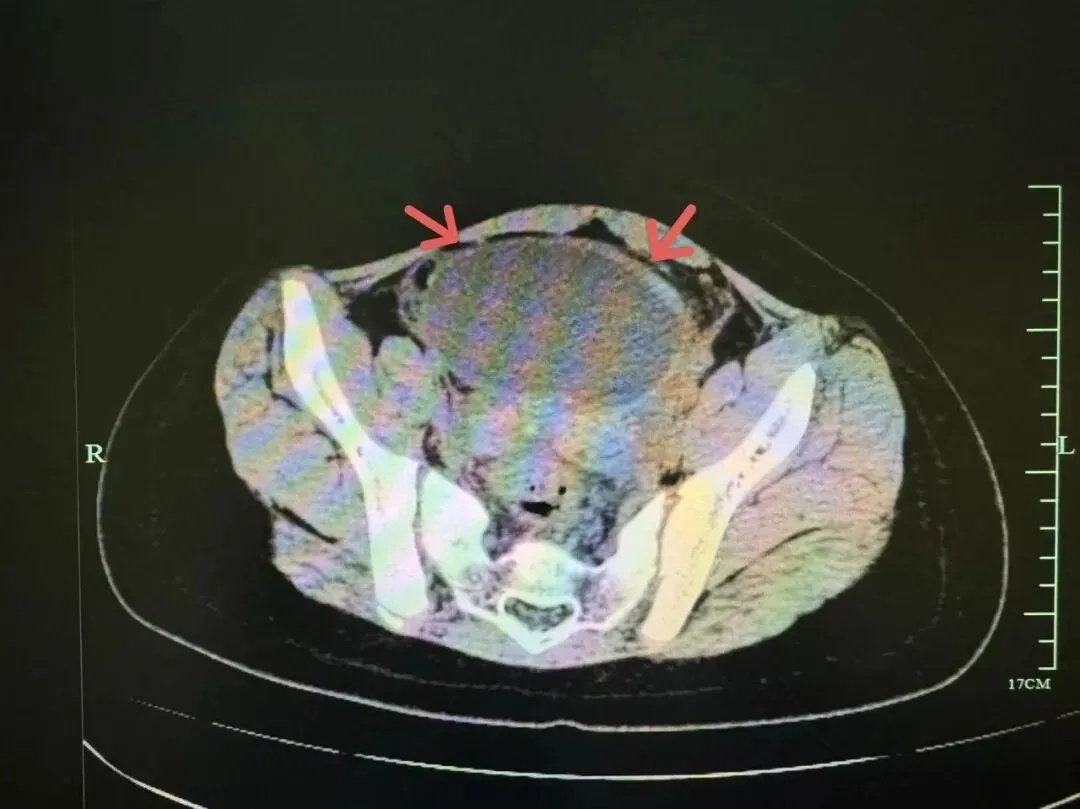

据B超和CT显示

小吉的盆腔内有一个约9.5cm的巨大卵巢囊肿,并且已发生了 “蒂扭转”,这是一种需要紧急手术的妇科急腹症!